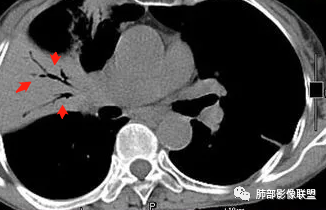

内部支气管稍扩张,直达远端,或受压变形、移位

均匀强化

内部血管走形自然,稍纤细

这里似乎稍增粗

4.血管造影征:肿瘤组织浸润引起间质增厚、肺泡壁破坏、肺泡腔充填,而周围充盈血管走行自然,未受肿瘤侵犯。血管造影征